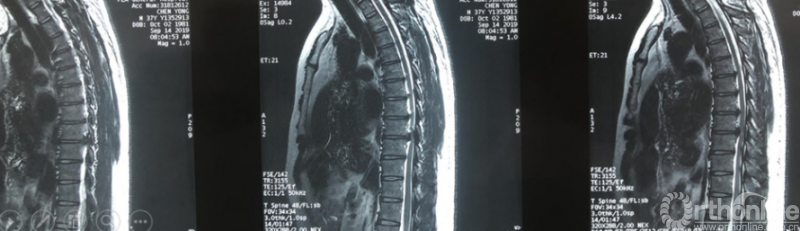

术前资料